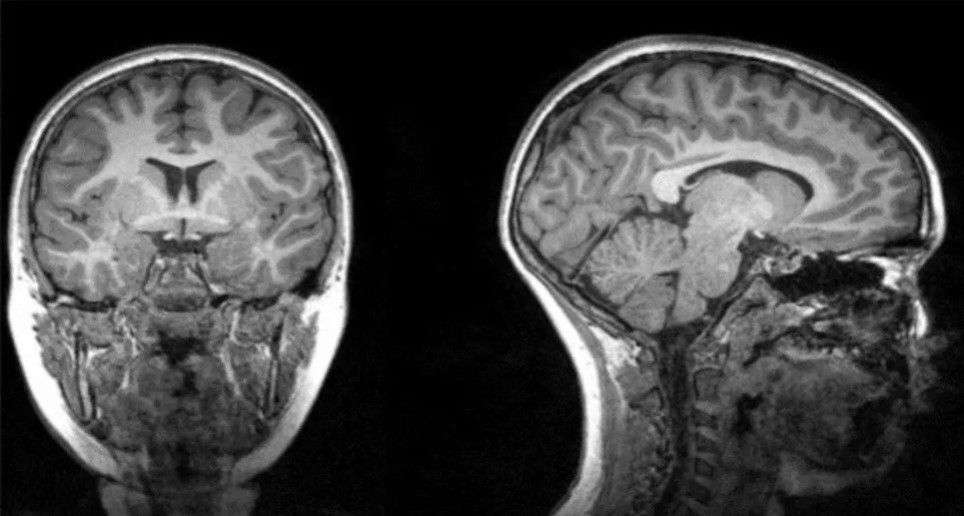

Ahora, un nuevo estudio a cargo de la Universidad Estatal de Georgia y el Instituto de Ternología de Georgia, en Estados Unidos, descubrió que los pacientes que se sometieron a terapia con oxígeno y que tuvieron altas temperaturas muestran un volumen reducido de materia gris en la región frontal-temporal del cerebro.

Esta investigación reveló que esta disminución del volumen de materia gris estaba asociada con el Covid-19. Y que se puede desarrollar hasta seis meses después de haber recibido el alta.

Los especialistas se valieron de tomografías computarizadas de 120 pacientes neurológicos, 58 de ellos positivos de Covid y 62 que formaban el grupo control.

Además, los investigadores encontraron que el volumen de materia gris en esta región se redujo significativamente más en los pacientes que recibieron oxigenoterapia en comparación con los pacientes que no la recibieron. Lo mismo ocurrió con los pacientes que presentaron fiebres altas.

Es por ello que llegaron a la conclusión que el Covid puede afectar la región frontal-temporal a través de fiebre o falta de oxígeno.